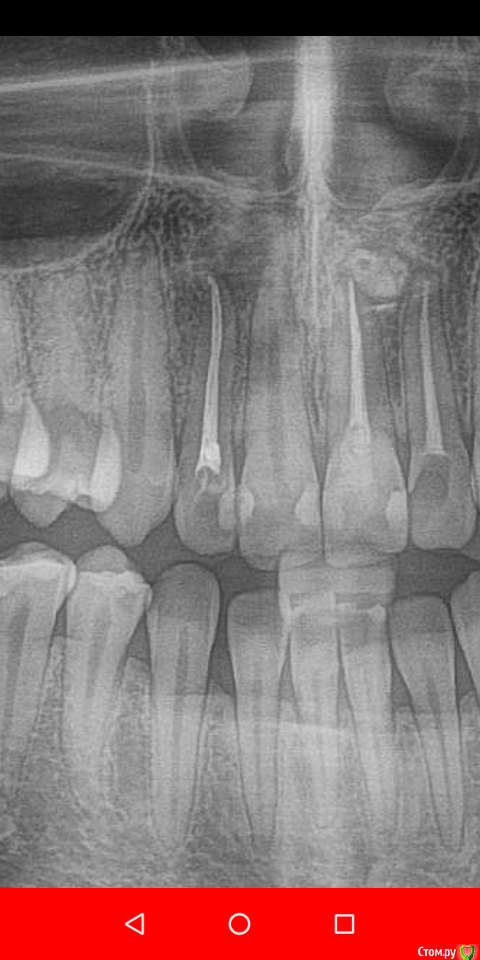

Daria_357 Опубликовано 21 августа, 2020 Поделиться Опубликовано 21 августа, 2020 Здравствуйте, резко появилась сильная неутихающая боль в 12м зубе, на третий день мне смогли оказать скорую помощь, поставив лекарство(убивающее нерв). Утром боль прошла, но опухло сильно лицо - вскрыли десну, поставив дренаж. Позже канал долго чистили и оставили временную пломбу на две недели. 18.08 приняли решение ставить постоянную пломбу. Первая пломбировка была неудачная-на снимке пломба не доходила до верхушки примерно на миллиметр. Вторая попытка закончилась так же, врач сомневалась, советовалась с коллегой, но оставила как было. На прицельном снимке видно, что не доходит в области "поворота" канала около 1мм, но у меня есть только ортопантомограмма, на ней видно только небольшую темную точку, и есть вид формы канала до пломбировки(прикрепила). По мнению врача, дойти дальше не получается так как канал изогнут. На мой вопрос почему тогда с временной пломбой пломбировка была идеальной(там пломба шла выше чем сейчас и истончалась к кончику), - врач сказала, что тогда канал был более узким, а сейчас она его расширила(?). Так же врач высказывала мнение, что если канал не запломб.до конца, то ничего страшного, - сделаем резекцию. Скажите, пожалуйста, стоит ли мне наставивать на перепломбировке уже сейчас, а не дожидаясь воспаления?Этот зуб отмечен синим. И второй вопрос по поводу плана лечения. Мне хотят с соседним передним зубом то же самое делать уже сейчас, так как есть опасения, что воспаление приблизится к нему. Верно ли это? Этот зуб отмечен красным. В этой же клинике мне года три назад вывели промбировочный материл за канал, достаточно много, но вариант, что воспаление из-за этого не подтвердили.Этот зуб отмечен зелёным. 2 Ссылка на комментарий